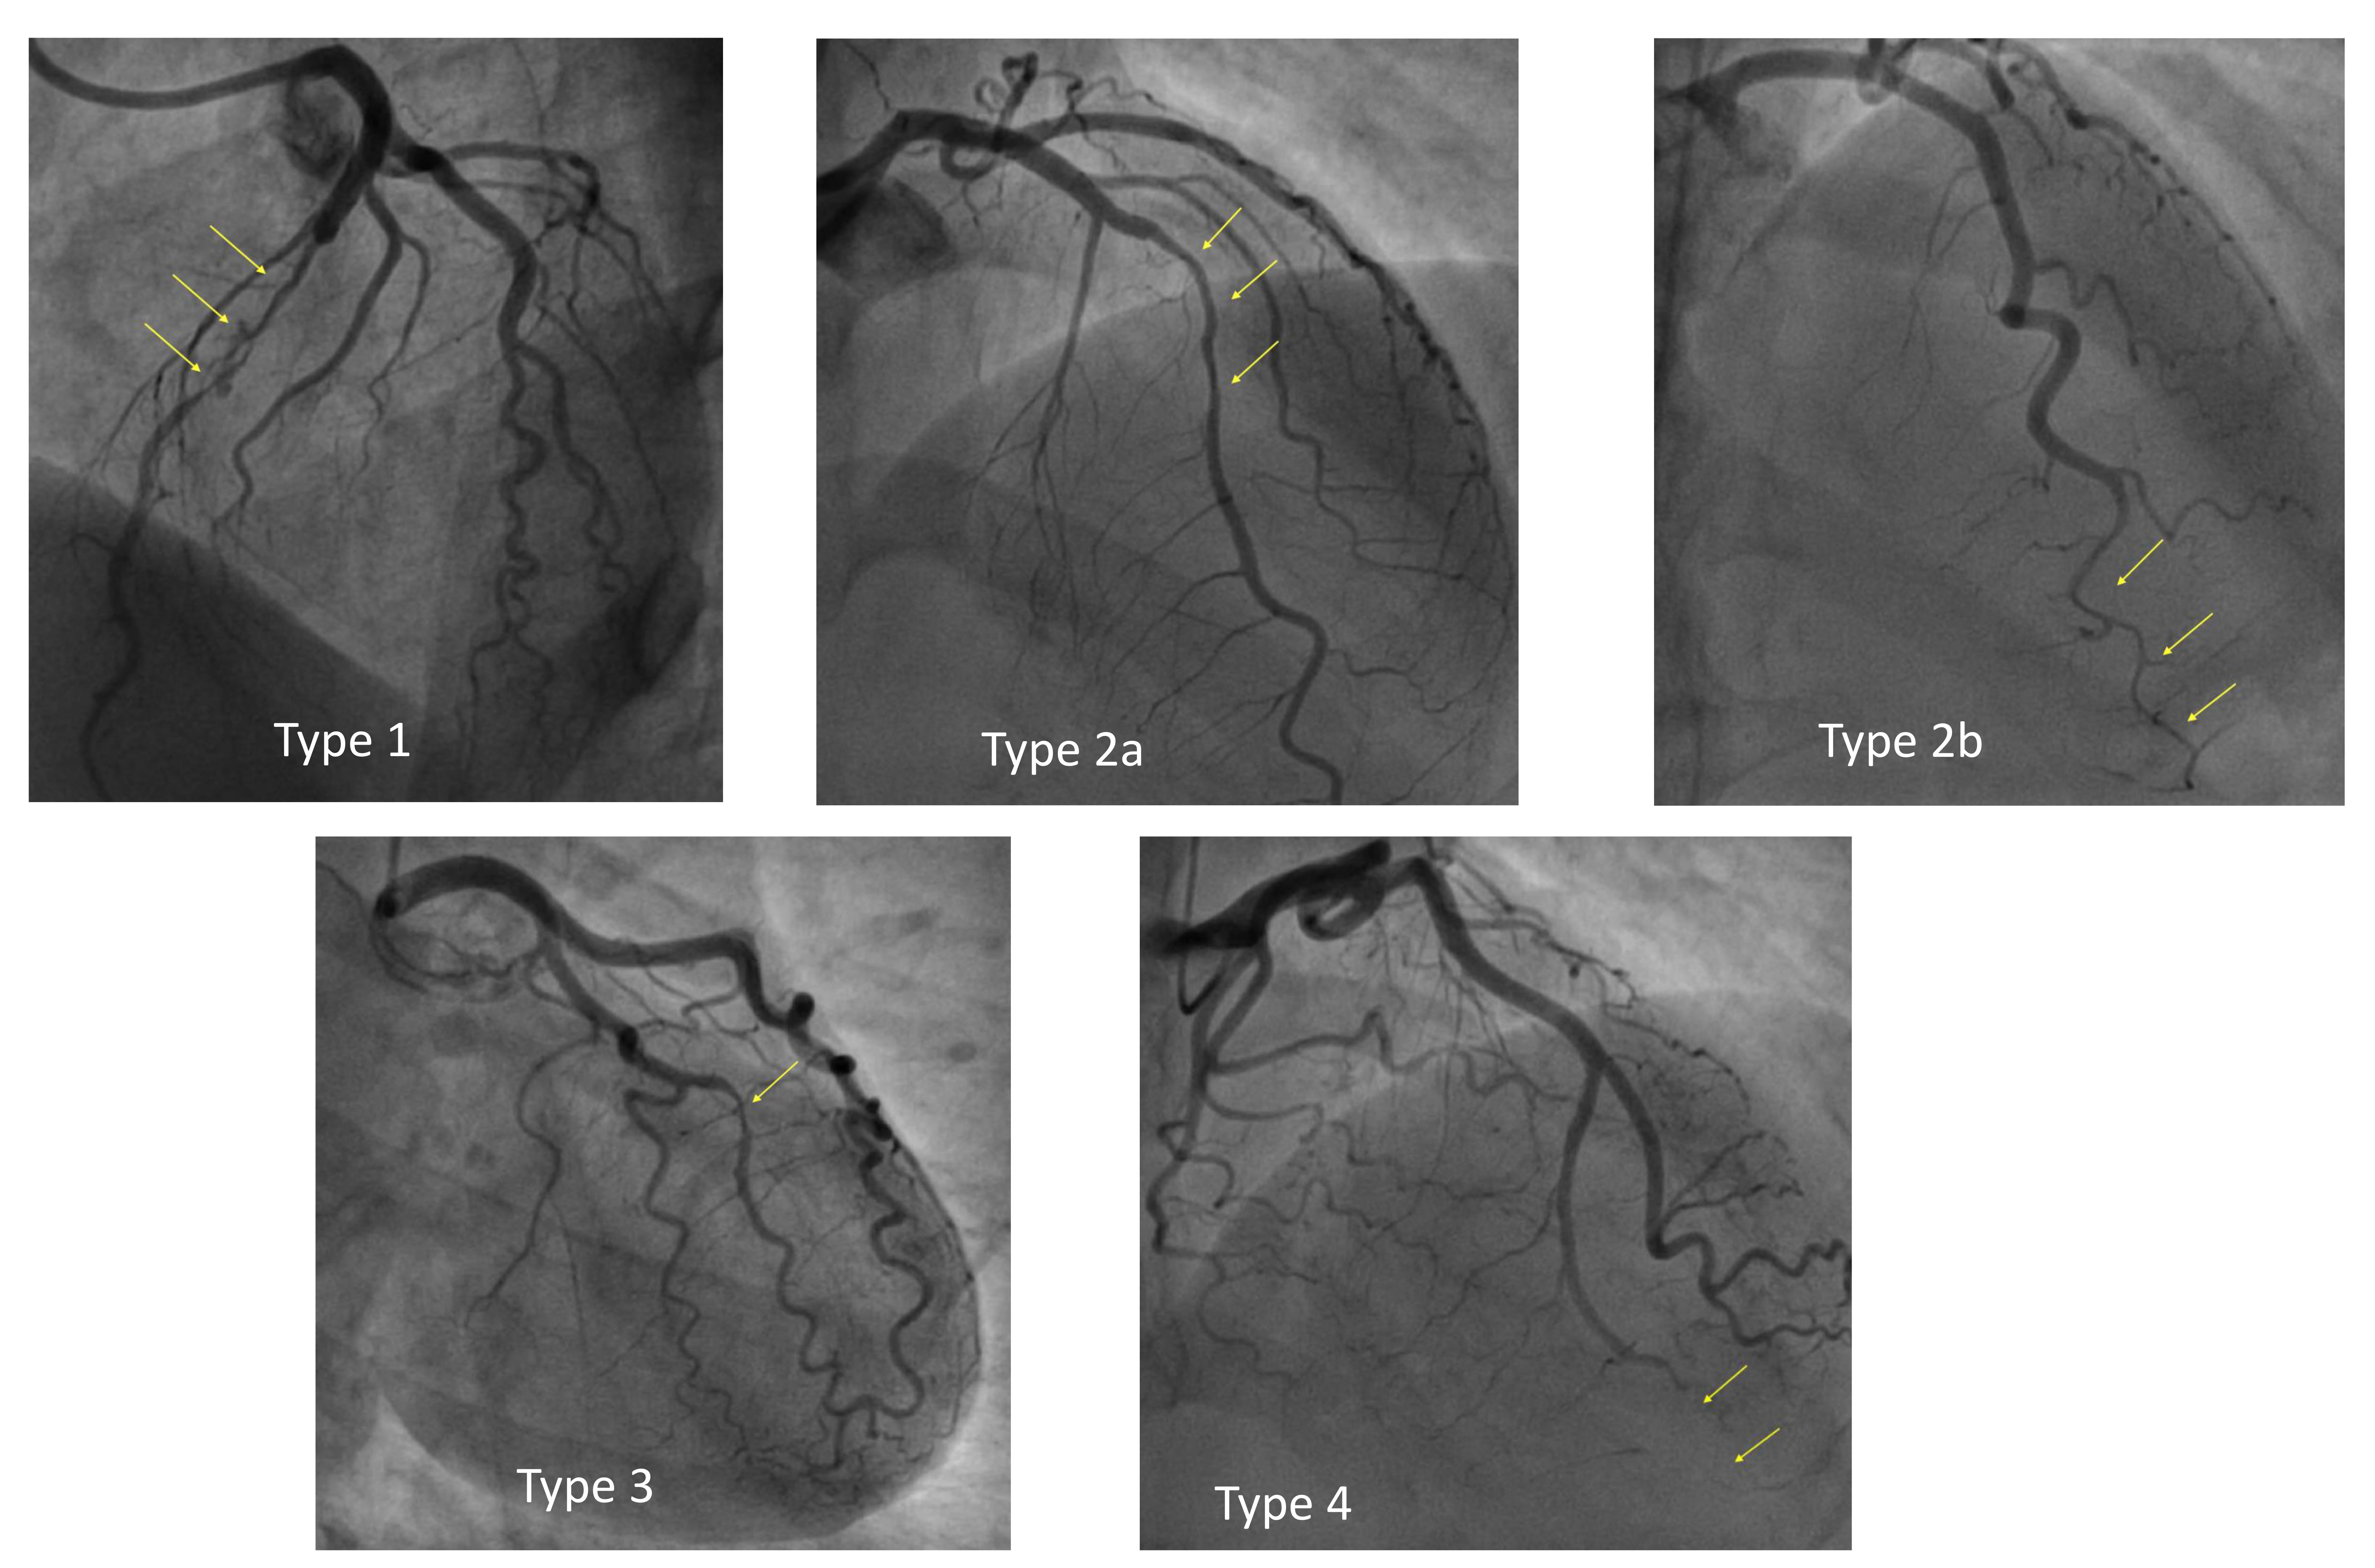

According to the classification proposed by the Canadian group and adopted by the consensus panel of the European Society of Cardiology, SCAD can be classified angiographically into the following categories [11, 12] (Fig. 1):

- Type 1: double-track image due to contrast stagnation in the false lumen—this represent the easiest pattern to interpret and is pathognomonic of SCAD, but it occurs in only 29% of SCADs.

- Type 2: presence of long narrowing of the vessel lumen, usually

- 2a: presence of distal restoration of the native coronary vessel caliber;

- 2b: extension of intramural hematoma up to the distality of the vessel with terminal “rat-tail” appearance.

- Type 3: focal narrowing of the lumen, indistinguishable from atherosclerotic lesions—about 4% of SCADs.

- Type 4: total vessel occlusion; its diagnosis is difficult as it can mimic complete thrombotic occlusion.

Fig. 1.

Angiographic classification of spontaneous coronary artery dissection (SCAD).